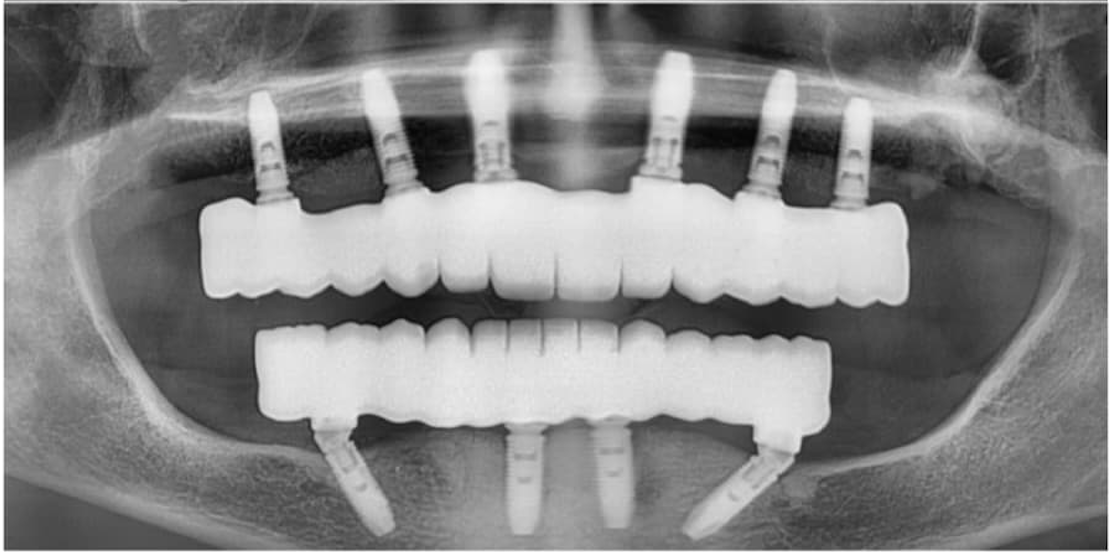

Immediate Loading Success

Before

Before treatment

After

After treatment